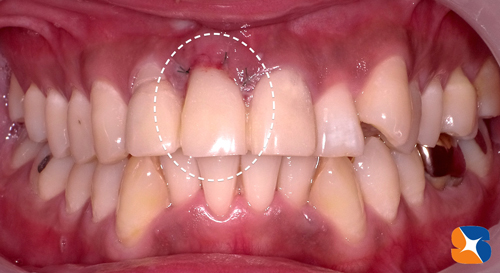

今年11月の初め。70代の患者様。20年来のかかりつけ歯科医院への治療後の帰り道。主訴は「もう吹っ切れた。痛みや腫れを訴えても、歯の掃除と薬だけ。なんかおかしい。たまたま通りかかっただけやけど診て欲しい」でした。

歯の根の周りの骨が大きく溶けて無くなってしまっている所が3箇所。

見た目も正直メチャクチャです。気の毒としかいいようがない。

よく今まで辛抱してきましたね。とにかく私が最短で、全ての悩みを解消いたします。

ビックリするような口元にしますので、任せておいて下さい。

残せる歯と、抜かなければならない歯の区分けが完了しました。

残した歯の治療は全て完了。最後に入れ歯を製作・装着すれば完成です。

12月28日、本日、入れ歯を装着して完了しました。

鏡を見た患者様は顔をくちゃくちゃにして「ここまで綺麗にしてもらえるとは思ってもいなかった。僅か2ヶ月でこんなにいい感じにしてもらえて感謝しています。嬉しくて、嬉しくて、しゃーない。右下の奥歯もずっと無いままで気にしていたので、ここは先生のお薦めのインプラントをしてもらうわ。来年もよろしくお願いします」でした。